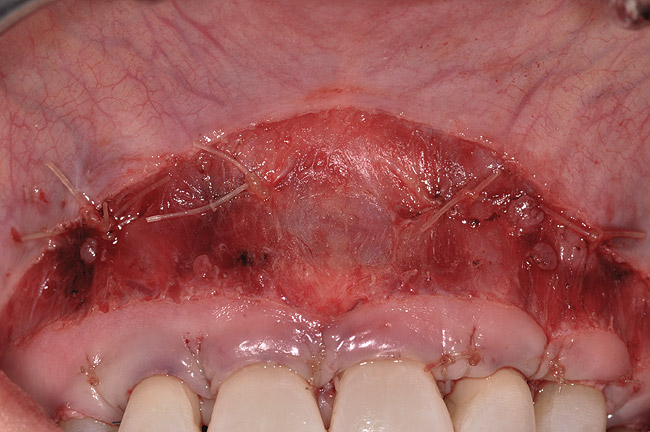

Once the entire surgical site has been closed, periosteal securing sutures, which secure the tissues repositioned superior to the reestablished mucogingival junction, complete the LAVA approach (Figure 5). These securing sutures will prevent any pull on the tissues coronally repositioned in the initial healing phase once the patient resumes normal function in the postoperative period.

Fig 5. Periosteal securing sutures.

Figure 5